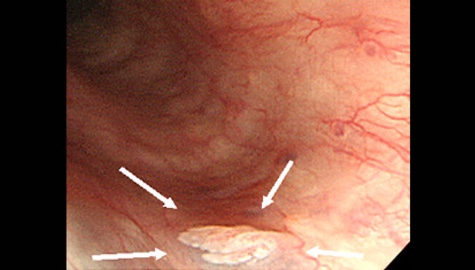

ハイビジョン内視鏡

胃腺腫の内視鏡写真です。 腫瘍の大きさから将来のがん化の可能性を考え、内視鏡治療を行っていくようになります。 この段階では症状は出現しませんが、このような早期の段階で腫瘍が発見できれば、内視鏡治療が可能になるのです。

インジゴカルミン特殊染色

胃腺腫のインジゴカルミン染色です。 腫瘍の部位が明瞭になります。

NBIハイビジョン内視鏡

NBI(狭帯域光観察)です。 さらに拡大ズームも用いることで、粘膜の表面構造や毛細血管の様子を観察し、腫瘍を詳細に調べます。